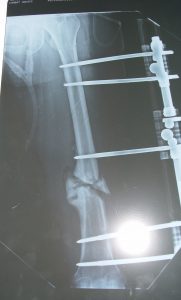

3. Defekt Psödoartrozlar

Genellikle birden çok kez cerrahi müdahele geçirmiş ya da osteomiyelitise bağlı kemik rezeksiyonu nedeniyle, çok nadiren de tümör rezeksiyonuna bağlı oluşmuş defektlerdir. Bilindiği gibi humerus da oluşan kısalık kimi otörlere göre 4cm bazılarına göre de 6 cm’ye kadar fonksiyonel bir yetersizlik ortaya çıkarmaz. Segment transportu monofokal osteogeneze göre daha komplike olduğundan 4-6 cm ‘lik defektler kadar psödoartroz mobil psödoartroz olarak kabul edilmelidir. Bunun üzerindeki defektlerde konvansiyonel olarak damarlı fibula grefti ya da allogreft uygulamalarının yanında, İlizarov’a göre segment transportu da bir tedavi seçeneğidir. Tümör rezeksiyonları dışındaki defektler genellikle 7 cm’nin altında olduğundan ( 4 cm kabul edilebilir defekt + 3 cm ilave kemik defekti) uygulanan teknik eksternal segment kaydırma olmalıdır. Bifokal osteogenezis olarak da isimlendirilen tedavinin süresini kısaltmak için önerilen bir yöntem de akut kısaltma ve tedrici uzatmadır. Aslında segment transporttan prensipte farklı olmayan bu uygulamada, hedef bölgenin kaynaması için geçen süre esnasında ekstremite uzatılacaktır.